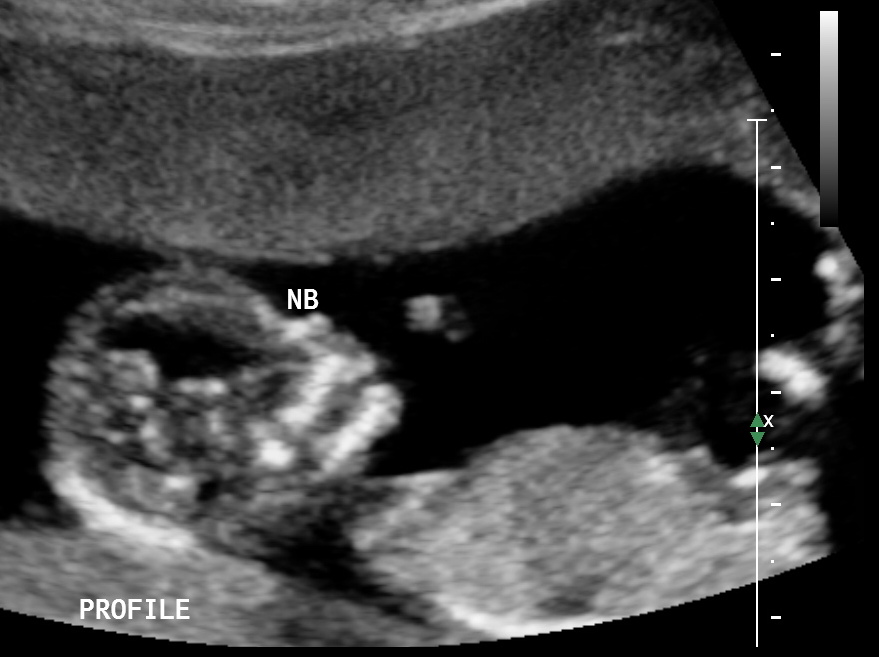

Attachment 37681

Girl based on 3rd pic

I'd guess girl on 3rd pic

Definite girl!